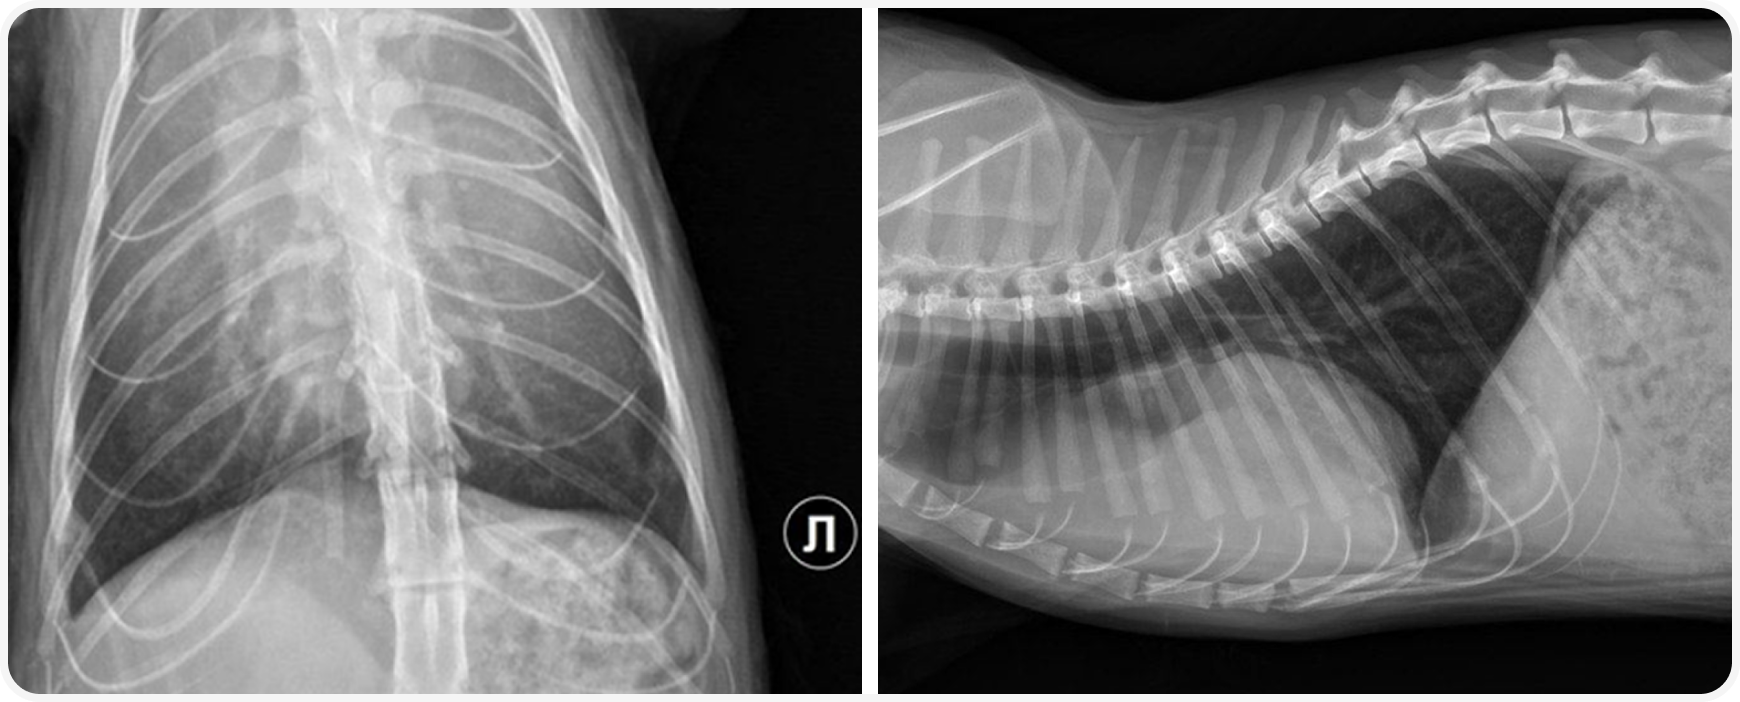

Пациент поступил в клинику из сторонней клиники на прием специалиста с жалобами на тяжелое дыхание. Врачом принято решения начать с диагностического рентгенологического исследования грудной клетки.

По результатам рентгенографии выявлено наличие добавочных структур средней рентгенологической плотности в вентральной части грудной клетки. Образование имеет масс-эффект, смещает силуэт сердца в каудо-дорсальном направлении.